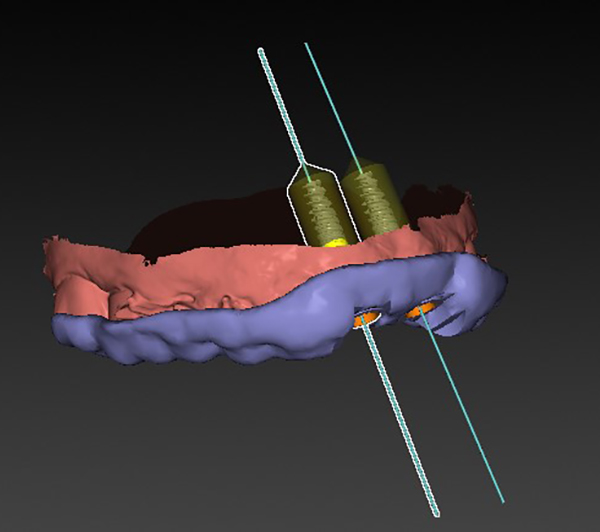

Extraction after forced eruption can allow for a much more favorable implant site compared with extraction alone. This is possible because the tension applied to the periodontal ligament during orthodontic tooth movement stimulates osteoblastic activity to induce new bone formation. As the tooth moves coronally during extrusion, soft tissue and bone attached to the periodontal fibers migrate in the same direction. As a result, forced eruption can be used to enhance the quality and quantity of both hard and soft tissue of future implant sites.

The special report presented below illustrates how orthodontic extrusion was successfully used to improve the periodontal architecture prior to the placement of two adjacent implants in the esthetic zone and thus allowed for a more ideal restorative result.